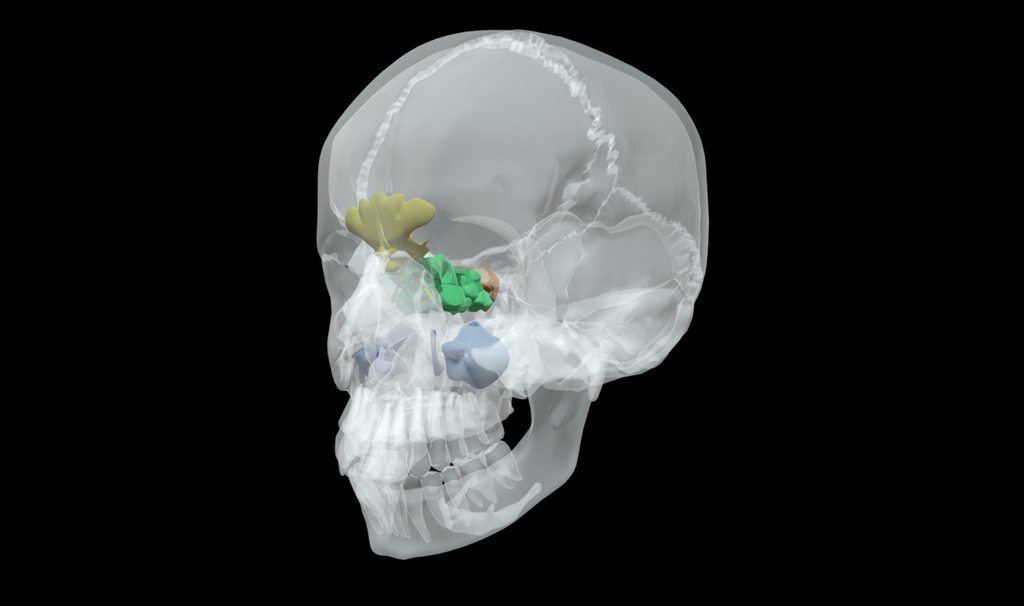

Inner Ear Scan

In chronic otitis with dense pars petrosa and middle ear opacity, cholesteatoma and associated complications can be diagnosed on CBCT.